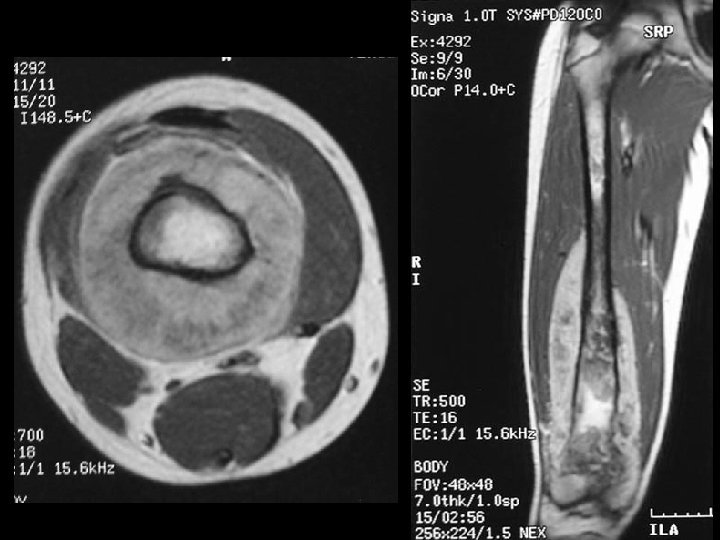

A 14 year old boy presents with pain and a mass above the knee. Take a look at the AP and lateral radiographs first.

Cross-sectional imaging Pictures are pretty, but diagnosis • established at histology MRI best for most tumors • optimal results at sites with experience – Role of CT limited • may assist in assessing tumor matrix – useful in directing biopsy –